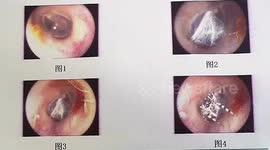

Chinese doctor removes pin from 7-month-old boy's body after he swallowed it

A doctor in southern China removed a pin from a 7-month-old boy’s body after he swallowed it.

The video, captured in the city of Chengdu in Sichuan Province on April 3, shows a doctor named Liu Yinghua using a tool to take a 2-centimetre-long pin out of a baby’s body during surgery.

According to reports, the baby mistakenly swallowed the pin when he was playing.

Fortunately, the pin was removed successfully and the baby has discharged from the hospital after two days of observation.